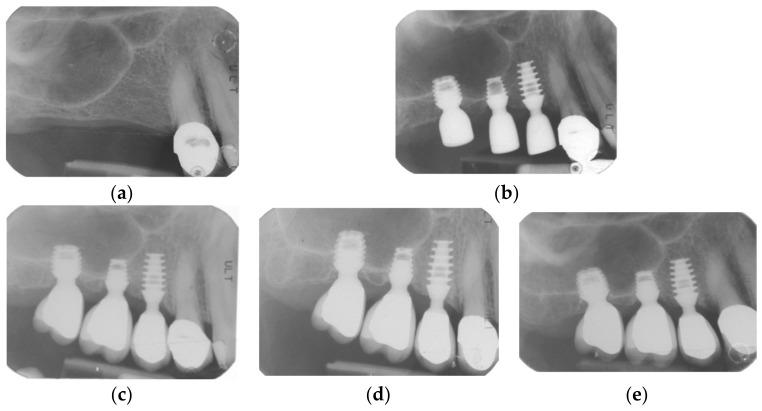

Recent short-term studies suggested the use of short and ultra-short implants in association with a modified osteotome sinus floor elevation (internal sinus lift) technique for the treatment of edentulous resorbed posterior maxilla. The aim of this retrospective study was to investigate this hypothesis in locking-taper implants with a mid-term follow-up of 5 years. Overall, 155 implants (32, 100, and 23 of, respectively, 5.0 mm, 6.0 mm, and 8.0 mm length) were positioned in the atrophic upper maxilla of 79 patients, and 151 implants were loaded with single crowns. Overall implant survival after 5 years was 94.84%. Implant survival for each length group was 93.75%, 94%, and 100% for 5.0, 6.0, and 8.0 mm length, respectively. Preoperative residual crestal bone height of 4.45 (1.3) mm increased to 9.25 (2.13) mm after implant placement and settled at 6.35 (1.73) mm after loading and at 5.25 (1.68) mm at follow-up. Elevation of the Schneiderian membrane was 4.8 (2.46) mm after implant placement, 3.06 (1.3) mm after loading, and 1.46 (1.06) mm at follow-up. Mean variations of peri-implant crestal bone loss and first bone-to-implant contact point were, respectively, -0.36 (1.3) mm and -0.62 (1.15) mm. It can be confirmed that internal sinus lift procedure revealed stable bone gain and negligible resorption at mid-term follow-up for atrophic upper crests with reduced height.

近期的短期研究表明,使用短种植体和超短种植体并结合改良骨凿上颌窦底提升术(内提升术)治疗上颌后牙区无牙颌吸收患者。本回顾性研究的目的是通过对锁定锥形种植体进行5年的中期随访来验证这一假设。总共155枚种植体(长度分别为5.0mm、6.0mm和8.0mm的种植体各32枚、100枚和23枚)植入79例患者的萎缩性上颌骨,151枚种植体上安装了单冠。5年后种植体总体存留率为94.84%。各长度组种植体的存留率分别为:5.0mm长度组93.75%,6.0mm长度组94%,8.0mm长度组100%。种植体植入前剩余牙槽嵴顶骨高度为4.45(1.3)mm,植入后增加到9.25(2.13)mm,加载后稳定在6.35(1.73)mm,随访时为(1.68)mm。种植体植入后上颌窦黏膜提升高度为4.8(2.46)mm,加载后为3.06(1.3)mm,随访时为1.46(1.06)mm。种植体周围嵴顶骨吸收和首次骨与种植体接触点的平均变化分别为-0.36(1.3)mm和-0.62(1.15)mm。可以确认,在内提升术中,对于高度降低的萎缩性上颌嵴,中期随访显示骨增量稳定且吸收可忽略不计。